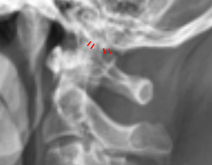

Image Type Cervical Spine X-Ray CT Scan MRI Scan Atlantodental Interval (ADI) Basion-Axial Interval Basion-Dens Interval (BDI) C2 Tilt C2–C7 Coronal Cobb Angle Cervical C2-7 lordosis C2-C7 Translation Chamberlain’s Line / McGregor’s Line Flexion-Extension George’s Line (Posterior Cervical Line) K-Line Interpedicular Distance (IPD) Occiput-C2 Angle Occipital Condyle–C1 Interval (CCI) Posterior Atlantodental Interval (PADI) Power’s ratio Sagittal Canal Diameter Sagittal Vertical Axis (SVA) Spinolaminar line Swischuk Line T1 Slope Torg/Pavlov Canal-to-Body Ratio